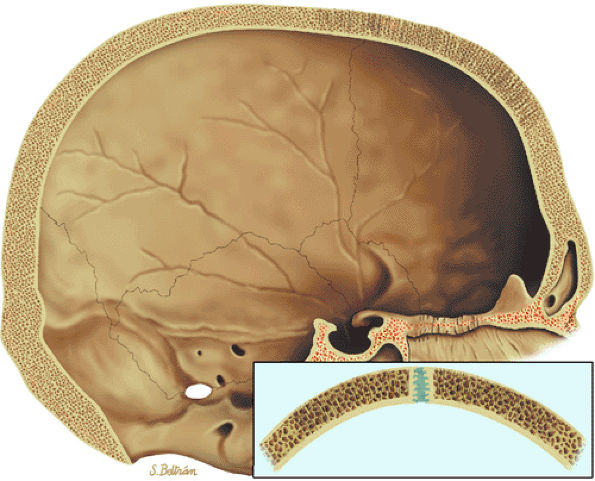

FIGURE 13.90 ● Paget—s disease of the skull. (A) Sagittal graphic illustration demonstrates an osteolytic lesion (arrows) involving the calvarium, consistent with osteoporosis circumscripta. (B) Axial CT image shows diploic widening and mixed lytic and sclerotic changes (cotton-wool appearance) (arrows) in the late stage of Paget—s disease.